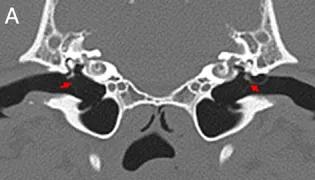

Deep learning models trained on scan images can aid vets in managing caseloads. AI tools can support vets in diagnosing disease, research has shown.A computer model has been trained to recognise a common disease in dogs with an encouraging success rate, underscoring its potential as a veterinary tool.The approach supports the use of AI for relatively straightforward tasks, to allow vets to concentrate on more complex tasks, according to the team behind the study. Scan imagesResearchers from the Royal (Dick) School of Veterinary Studies, the Roslin Institute and the University of Edinburgh’s School of Informatics developed their model using CT scan images of dogs’ middle ears – a part of the ear that is frequently affected by disease.The model was trained to recognise disease using about 500 images, some that showed signs of disease and others that did not, which had been manually interpreted by veterinary experts. This number is fewer than the several thousands that would typically be needed for many AI studies, which would be resource-intensive to generate.The AI tool was able to make correct diagnoses in 85 per cent of cases. Experts say the result is robust for a relatively small sample size, demonstrating the validity of the approach, and could be improved if additional images were annotated. AI can be deployed to diagnose disease with reliable accuracy. Diagnosis potentialThe application of AI in this way, which is established in human medicine, could be made to various veterinary medicine challenges, potentially including those that are traditionally difficult to diagnose by eye. This would save time and money in making diagnoses, the team says.A bank of veterinary medical images, annotated by vets, would be required to enable adoption of AI in veterinary diagnoses, and could be applied across a range of conditions, the team suggests. Vet schools and hospitals such as the R(D)SVS have banks of images, but a sufficient number have to be annotated to train algorithms.The study was conducted by a masters degree student in the School of Informatics. Our study showed that deep learning computer models can be trained to determine whether or not disease is present in a veterinary CT image. Even training our model on a relatively small number of images had encouraging results. “This outcome is a call to arms to gather resources to enable models of this type, for various veterinary conditions. Dr Chris Banks, Roslin Institute “This is a great example of how AI can be put to use to help veterinarians, rather than replace them.” Dr Tobias Schwarz, Royal (Dick) School of Veterinary Studies Tags Vet School This article was published on 2025-09-10